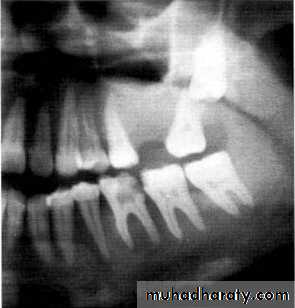

Dentigerous CystIt forms around the crown of an unerupted or supernumerary tooth at CEJ.

Some dentigerous cysts are eccentric, developing from the lateral aspect of the follicle so that they occupy an area beside the crown instead of above the crown.

It displace and resorb adjacent teeth.

It commonly displaces the associated tooth

in an apical direction.